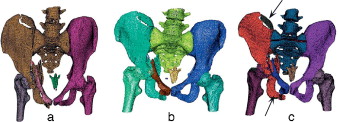

Las Figura 3 , Figura 4 and Figura 5 muestran un caso de las regiones anatómicas construidas mediante los algoritmos analizados. El nivel de descomposición del dominio geométrico alcanzado por cada una de ellas se observa a través de la representación de las isosuperfices (regiones anatómicas) en diferentes colores.

|

|

|

Figura 3. Resultados obtenidos al aplicar los 3 algoritmos a un conjunto de imágenes pertenecientes a la articulación de la rodilla: a) aplicando pyFormex; b) aplicando VTK, y c) aplicando el algoritmo propuesto con t = 0,6. |

|

|

|

Figura 4. Resultados obtenidos al aplicar los 3 algoritmos a un conjunto de imágenes pertenecientes al hombro: a) aplicando pyFormex; b) aplicando VTK, y c) aplicando el algoritmo propuesto con t = 0,2. |

|

|

|

Figura 5. Resultados obtenidos al aplicar los 3 algoritmos a un conjunto de imágenes pertenecientes a una pelvis fracturada: a) aplicando pyFormex; b) aplicando VTK, y c) aplicando el algoritmo propuesto con t = 0,6. |

En la figura 3 se aprecian las isosuperficies del modelo de la rodilla después de aplicar los 3 algoritmos. pyFormex no separó el fémur de la tibia (fig. 3 a) en ninguna de las 2 piernas, mientras que con la VTK solo se logró separar el fémur y la tibia de la pierna izquierda (fig. 3 b).

El algoritmo propuesto separó satisfactoriamente (fig. 3 c) el fémur de la tibia en ambas piernas. Las rótulas derecha e izquierda fueron identificadas correctamente por los 3 algoritmos.

En la región anatómica del hombro (fig. 4 ) el objetivo fundamental era la obtención por separado de las clavículas, los húmeros y las escápulas. pyFormex identificó correctamente las clavículas pero no separó los húmeros de las escápulas (fig. 4 a). La VTK identificó solamente la clavícula derecha y tampoco separó los húmeros de las clavículas (fig. 4 b).

El algoritmo propuesto identificó correctamente las clavículas y solo separó el húmero izquierdo de la clavícula correspondiente (fig. 4 c).

Finalmente, se utilizaron imágenes de una pelvis fracturada (fig. 5 ). En este caso, pyFormex identificó correctamente el fémur derecho, pero no el izquierdo, al que identificó como parte del hueso iliaco izquierdo. En cuanto al hueso iliaco derecho, lo identificó como parte del sacro (fig. 5 a). La VTK (fig. 5 b) identificó correctamente los huesos iliacos, el fémur derecho y el izquierdo, y el sacro, pero no identificó la fractura de la cresta iliaca izquierda.

El algoritmo propuesto separó los mismos huesos que la VTK, además de identificar correctamente la fractura en la cresta iliaca izquierda como un elemento separado (señalada en la fig. 5 c).

En todos los casos se identificó correctamente la fractura del pilar anterior izquierdo desde el trasfondo acetabular hasta el pubis (señalada en la fig. 5 c). En este tipo de imágenes, el objetivo era determinar las fracturas existentes además de los huesos que constituyen esta región anatómica.